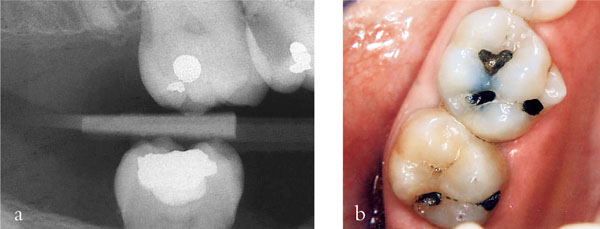

Fig 1-6 (a,b) A radiograph (a) and clinical appearance (b) of an extensive carious lesion on the distal aspect of the UR6 of a young teenage patient. In such a situation complete caries removal in one visit risks exposing the pulp. Stepwise excavation reduces this risk.

Fig 1-6 (c–g) In this procedure, access to the caries was gained (c) at the first appointment and peripheral caries removed leaving soft carious dentine pulpally (d). A provisional restoration was placed, using a polycarboxylate cement (e) and then left for 6 to 12 months. When the restoration was removed (f) and pulpal caries excavated no pulpal exposure occurred (g) (Series of images courtesy of Dr Nicola Innes).